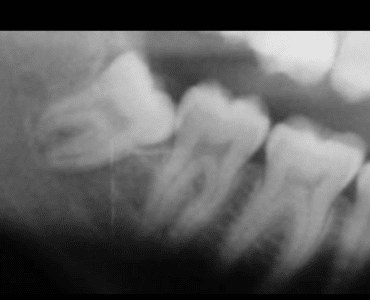

Nelle prime tre immagini: molare a contatto del nervo così come arrivato in ambulatorio prima della terapia.

Immagini successive: a fine terapia estrusiva ortodontica (Ortodonzia Estrattiva) il dente del giudizio nelle prime due foto appare sollevato e lontano dal nervo. Nell’ultima foto è già stato estratto; da notare il livello osseo che l’estrusione ortodontica ha creato distalmente e vicino al secondo molare